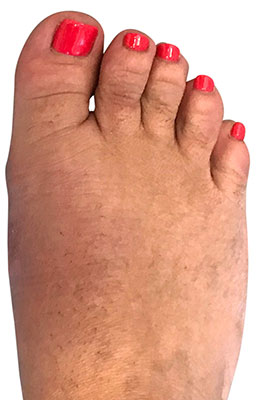

Minimally Invasive Bunion Surgery featuring the miniBunon™ System and Tailors Bunionectomy

Melissa is a 32-year-old businesswoman who could not be off her foot post-surgery, yet she had a severely painful bunion. We performed our miniBunon™ System (our trademarked minimally invasive bunion surgery) and had a dramatic correction with no downtime. Melissa continued to work after her bunion surgery and was back in shoes and full activity at 5 weeks. Melissa could not believe the results of her Bunionectomy resulting in no bony bump, no scar and amazing motion. “After” picture taken immediately following surgery. Note the bunion and bunionette (Tailor’s bunion) in the before picture.